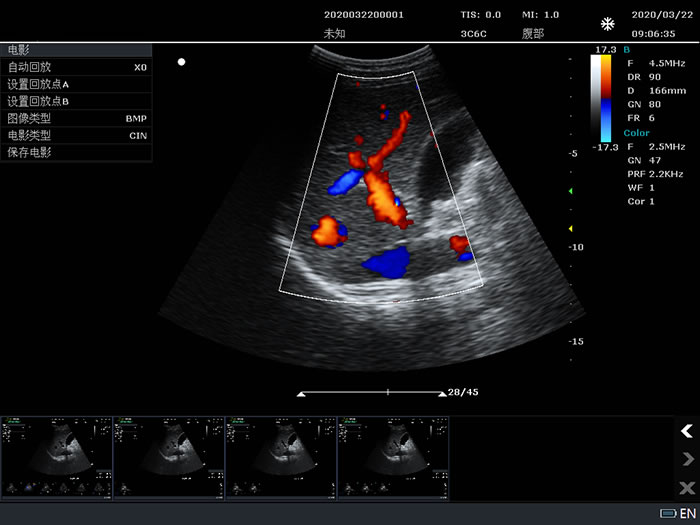

Color(彩色多谱勒)模式

3.4 Color/PDI模式

PRF:≥15档,0.6KHz – 11.7KHz

彩色图谱(color map):≥4种

彩色相关:≥8档

后处理:≥4档